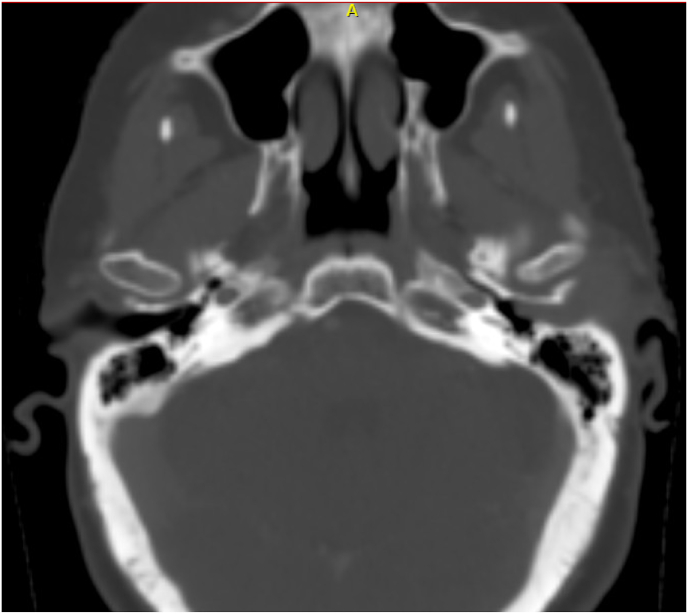

Abstract Image